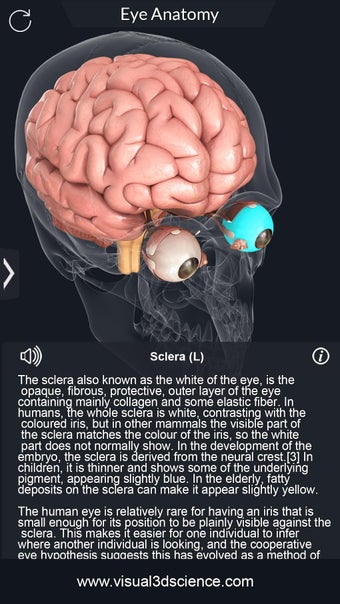

Изучите в деталях человеческий глаз и его анатомию с помощью этого простого в использовании бесплатного приложения для Android. Он позволяет масштабировать и вращать на 360° вокруг высокореалистичной 3D-модели глаза, а также рисовать на экране или прослушивать звуковое произношение каждого термина.

Вы можете выбрать X- просмотр луча, скрытие и отображение отдельных частей глаза, а также рисование или белый цвет на экране и обмен снимками экрана, звуковое произношение для всех анатомических терминов и многое другое.

Каждая часть разделена на отдельный вид, где вы можете можно увидеть название детали и ее расположение на глаз.